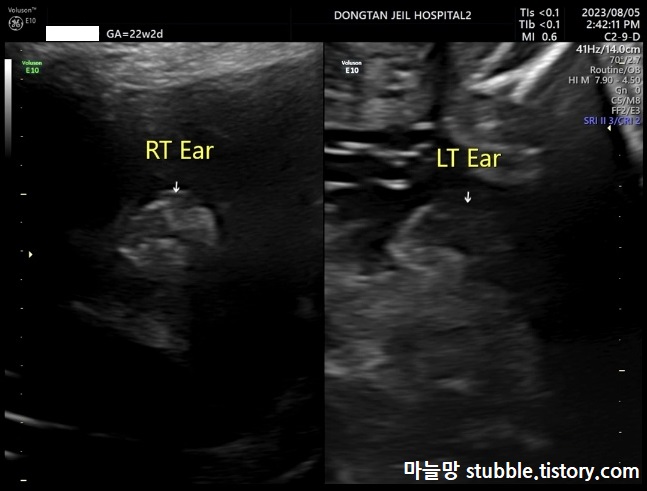

13. 안구의 여부 (Eye ball) / 오른쪽 왼쪽 귀의 여부(RT Ear, LT Ear)

(2) 오른쪽 왼쪽 귀의 여부(RT Ear, LT Ear)

귀도 양쪽이 모두 형성이 되어 있는 것으로 보입니다.